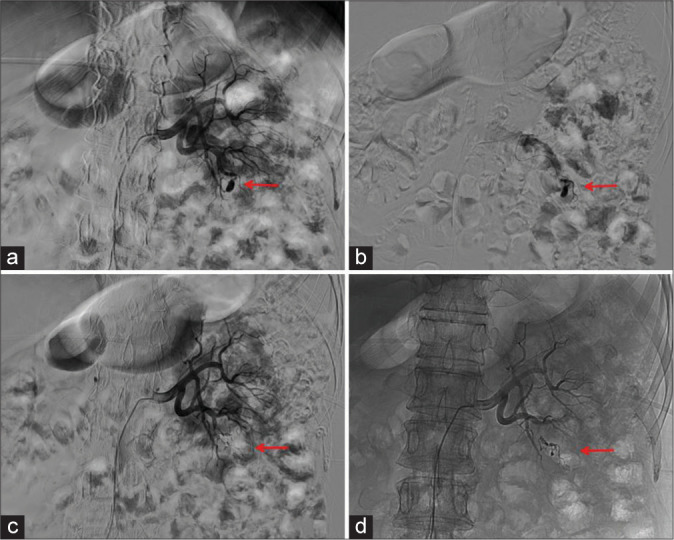

Results: A total of 32 pseudoaneurysms were embolized in 31 patients with peripheral pseudoaneurysms. All pseudoaneurysms originated from visceral arteries. Among them, 29 pseudoaneurysms were embolized with medical adhesive alone, and three pseudoaneurysms were embolized with coil-assisted medical adhesive. After endovascular embolization with medical adhesive, all pseudoaneurysms were successfully embolized. Technical success was 100%. All patients experienced cessation of bleeding after endovascular embolization with medical adhesive, and there were no serious post-operative complications. Clinical success was 100%. During the follow-up period, two patients experienced recurrent bleeding but no pseudoaneurysm recurrence was observed.

Abstract Image